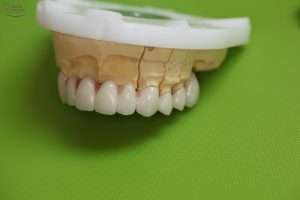

Az elkészült fémkerámia körhíd mestermintán. A magasabb esztétika érdekében a fogak közötti részen a fogtechnikus rózsaszín kerámiát használ, mely megegyezik az íny színével és takarja a fekete lyukakat. A fekete lyukak (fekete háromszöghatás), ami a fognyakak között alakul ki, rendkívül előnytelen esztétikai képet tud mutatni.

Az elkészült fémkerámia körhíd mestermintáról levéve szemből

Az elkészült fémkerámia körhíd mestermintáról levéve, alulnézetből